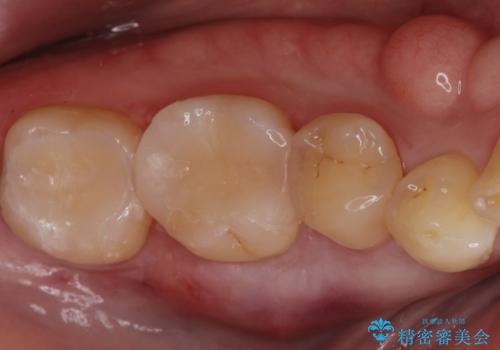

セラミックインレー。

古い樹脂の材料をとりe-maxの詰め物で治療を行いました。

適合の良い詰め物が入りました。